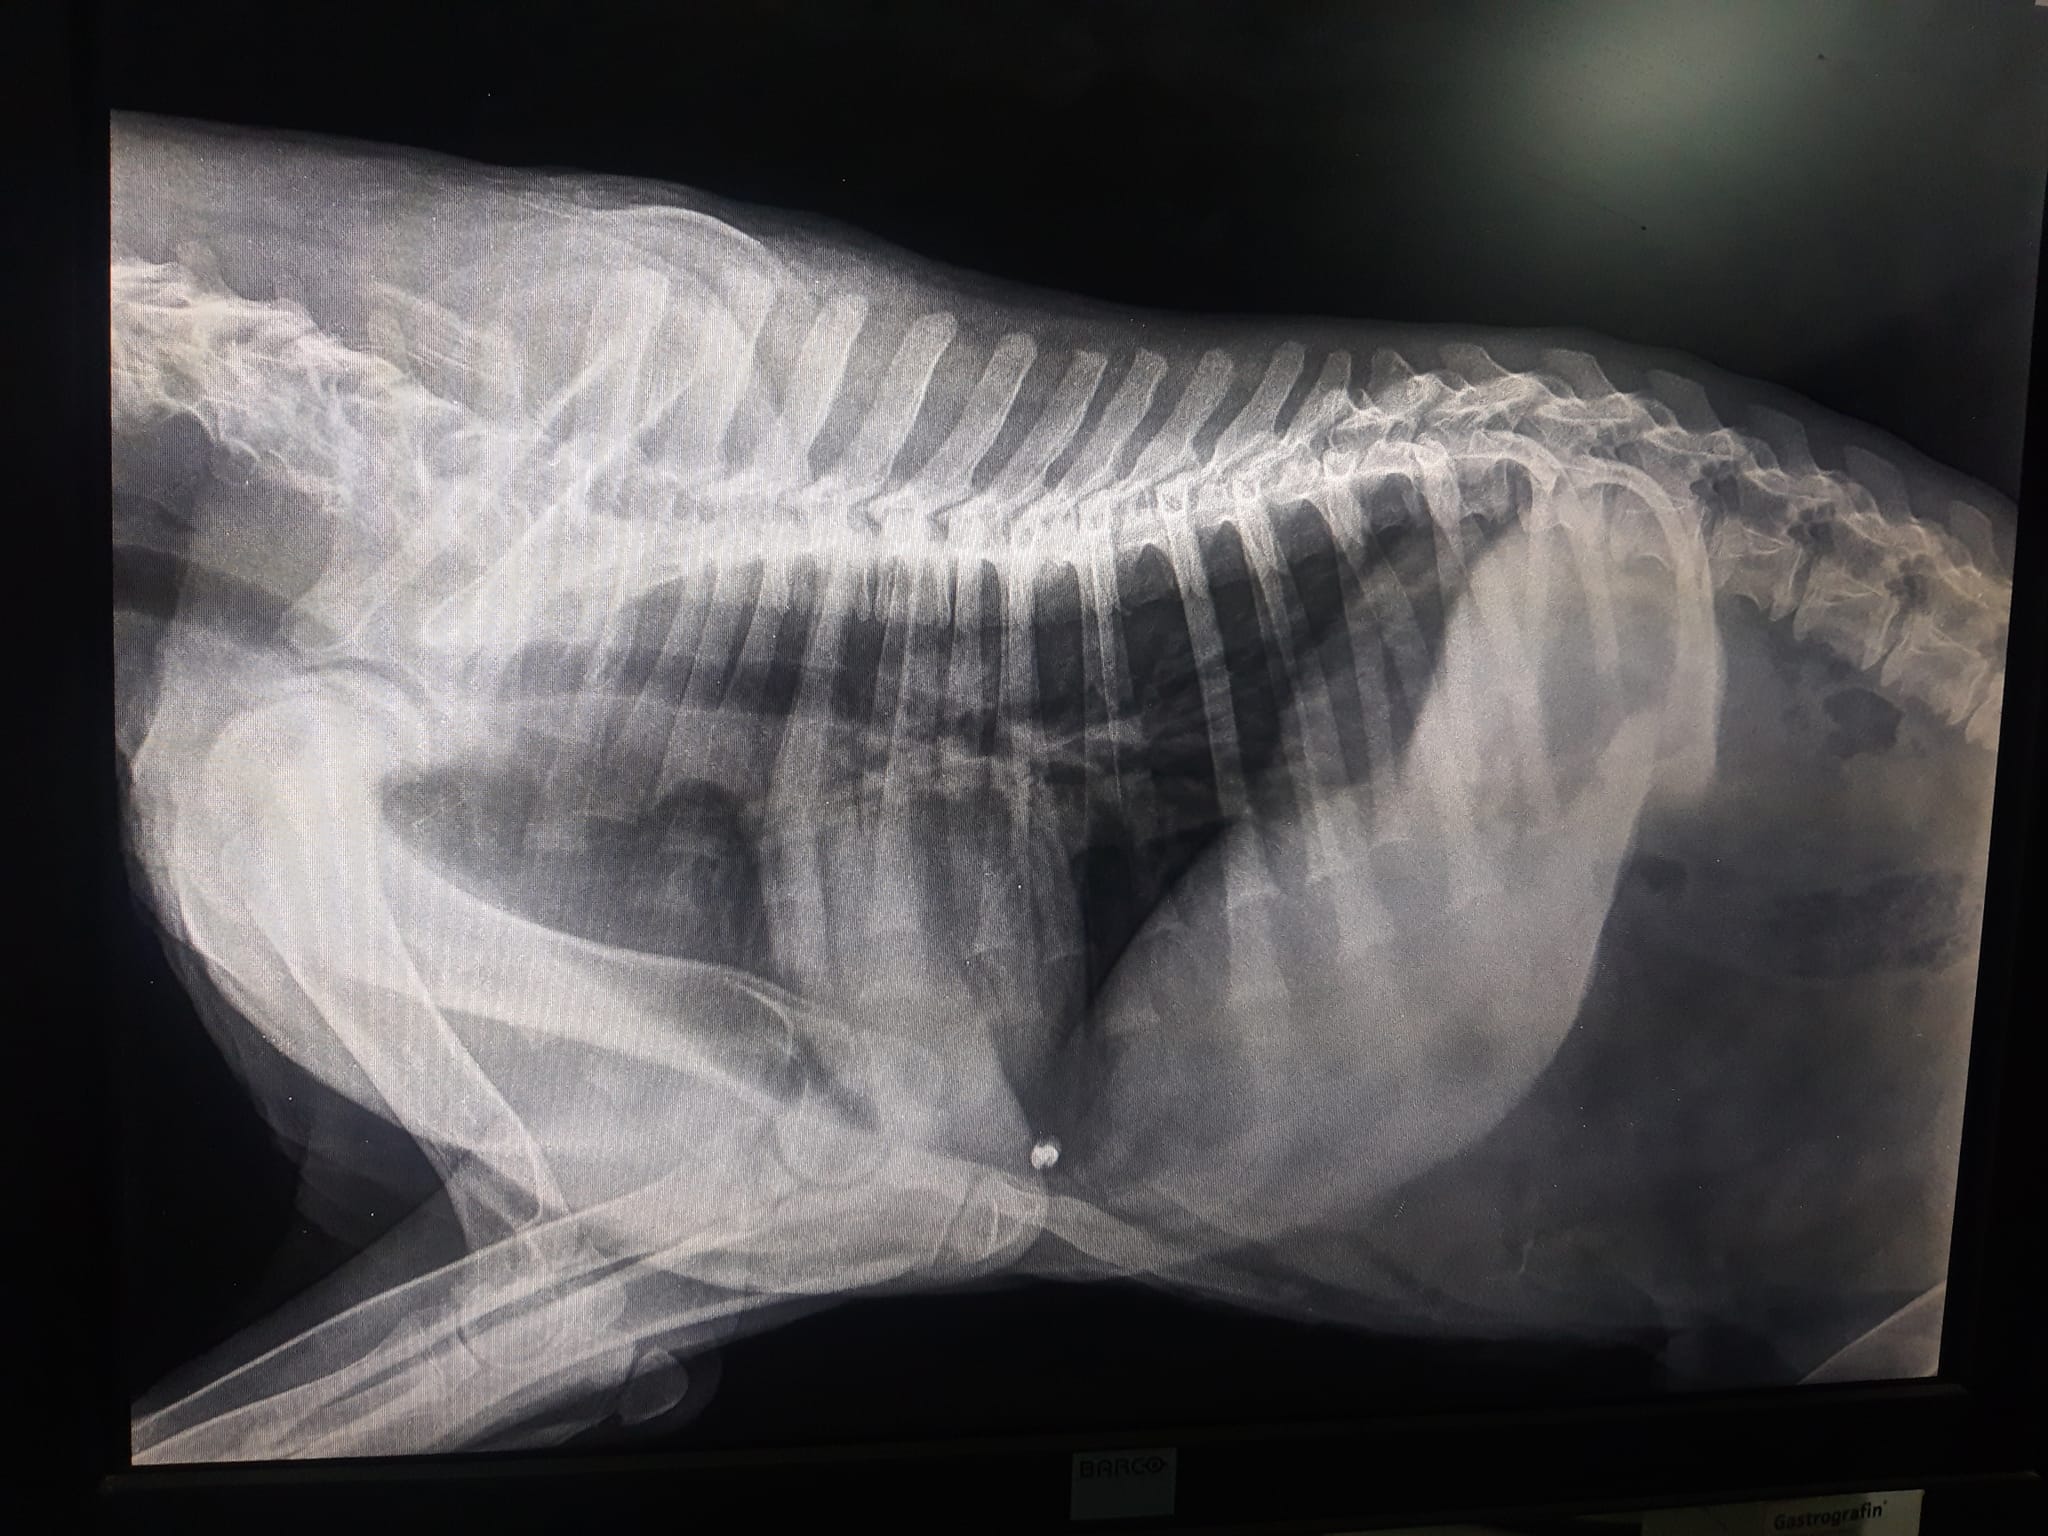

Έκκληση για να καλυφθούν τα έξοδα περίθαλψης ενός κουταβιού που βρέθηκε παράλυτο στα πίσω πόδια έξω από τη Φλώρινα πάνω στις ράγες του τρένου απευθύνει  μέσω facebook η Ναταλία Σαχινίδου. Το ζώο όπως έδειξαν οι ακτινογραφίες έχει πυροβοληθεί με αεροβόλο.

Στις ακτινογραφίες που διενεργήθηκαν ανευρέθηκε βλήμα αεροβόλου όπλου στη θωρακική κοιλότητα οπισθοστερνικά, έντονα ελαττωμένη οστική πυκνότητα ιδιαίτερα στα οπίσθια άκρα, αξιοσημείωτη χαλαρότητα αμφοτερόπλευρα και στα δύο γόνατα πού συνάδει με εικόνα ρήξεως πρόσθιου χιαστού. Στην ουσία όπως θα δείτε και στις ακτίνες μετά από ένα σημείο το στο σχεδόν παύει να υπάρχει, αν όχι από όταν γεννήθηκε τότε στην πορεία το ζώο όσο πιο ατρωφικο γινόταν το οστό τόσο τον οδηγούσε στην κατάσταση που είναι τώρα. Ο Αslan έχει 10% πιθανότητες όχι να περπατήσει αλλά να σταθεί, παρόλα αυτά δεν θα τα παρατήσουμε αφού έχει μια ζωντάνια και μια θέληση για ζωή που θαυμάζω μετά όλο αυτό που του συνέβη στους 5 μήνες της ζωής του ... Θα ακολουθήσουμε φαρμακευτική αγωγή για την θρέψη των οστών και σε 1 μήνα θα πρέπει να πάμε ξανά να δούμε πως πάμε! Για όποιον θέλει να βοηθήσει αυτοί είναι οι λογαριασμοί του κτηνιάτρου κ Νίκου πατσινακιδη.